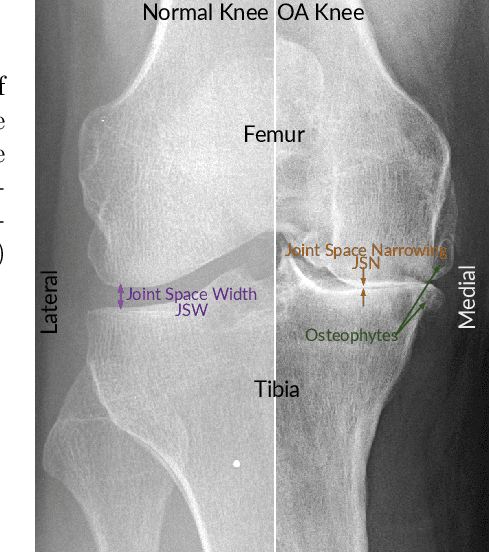

Abstract:Knee osteoarthritis (OA) is very common progressive and degenerative musculoskeletal disease worldwide creates a heavy burden on patients with reduced quality of life and also on society due to financial impact. Therefore, any attempt to reduce the burden of the disease could help both patients and society. In this study, we propose a fully automated novel method, based on combination of joint shape and convolutional neural network (CNN) based bone texture features, to distinguish between the knee radiographs with and without radiographic osteoarthritis. Moreover, we report the first attempt at describing the bone texture using CNN. Knee radiographs from Osteoarthritis Initiative (OAI) and Multicenter Osteoarthritis (MOST) studies were used in the experiments. Our models were trained on 8953 knee radiographs from OAI and evaluated on 3445 knee radiographs from MOST. Our results demonstrate that fusing the proposed shape and texture parameters achieves the state-of-the art performance in radiographic OA detection yielding area under the ROC curve (AUC) of 95.21%